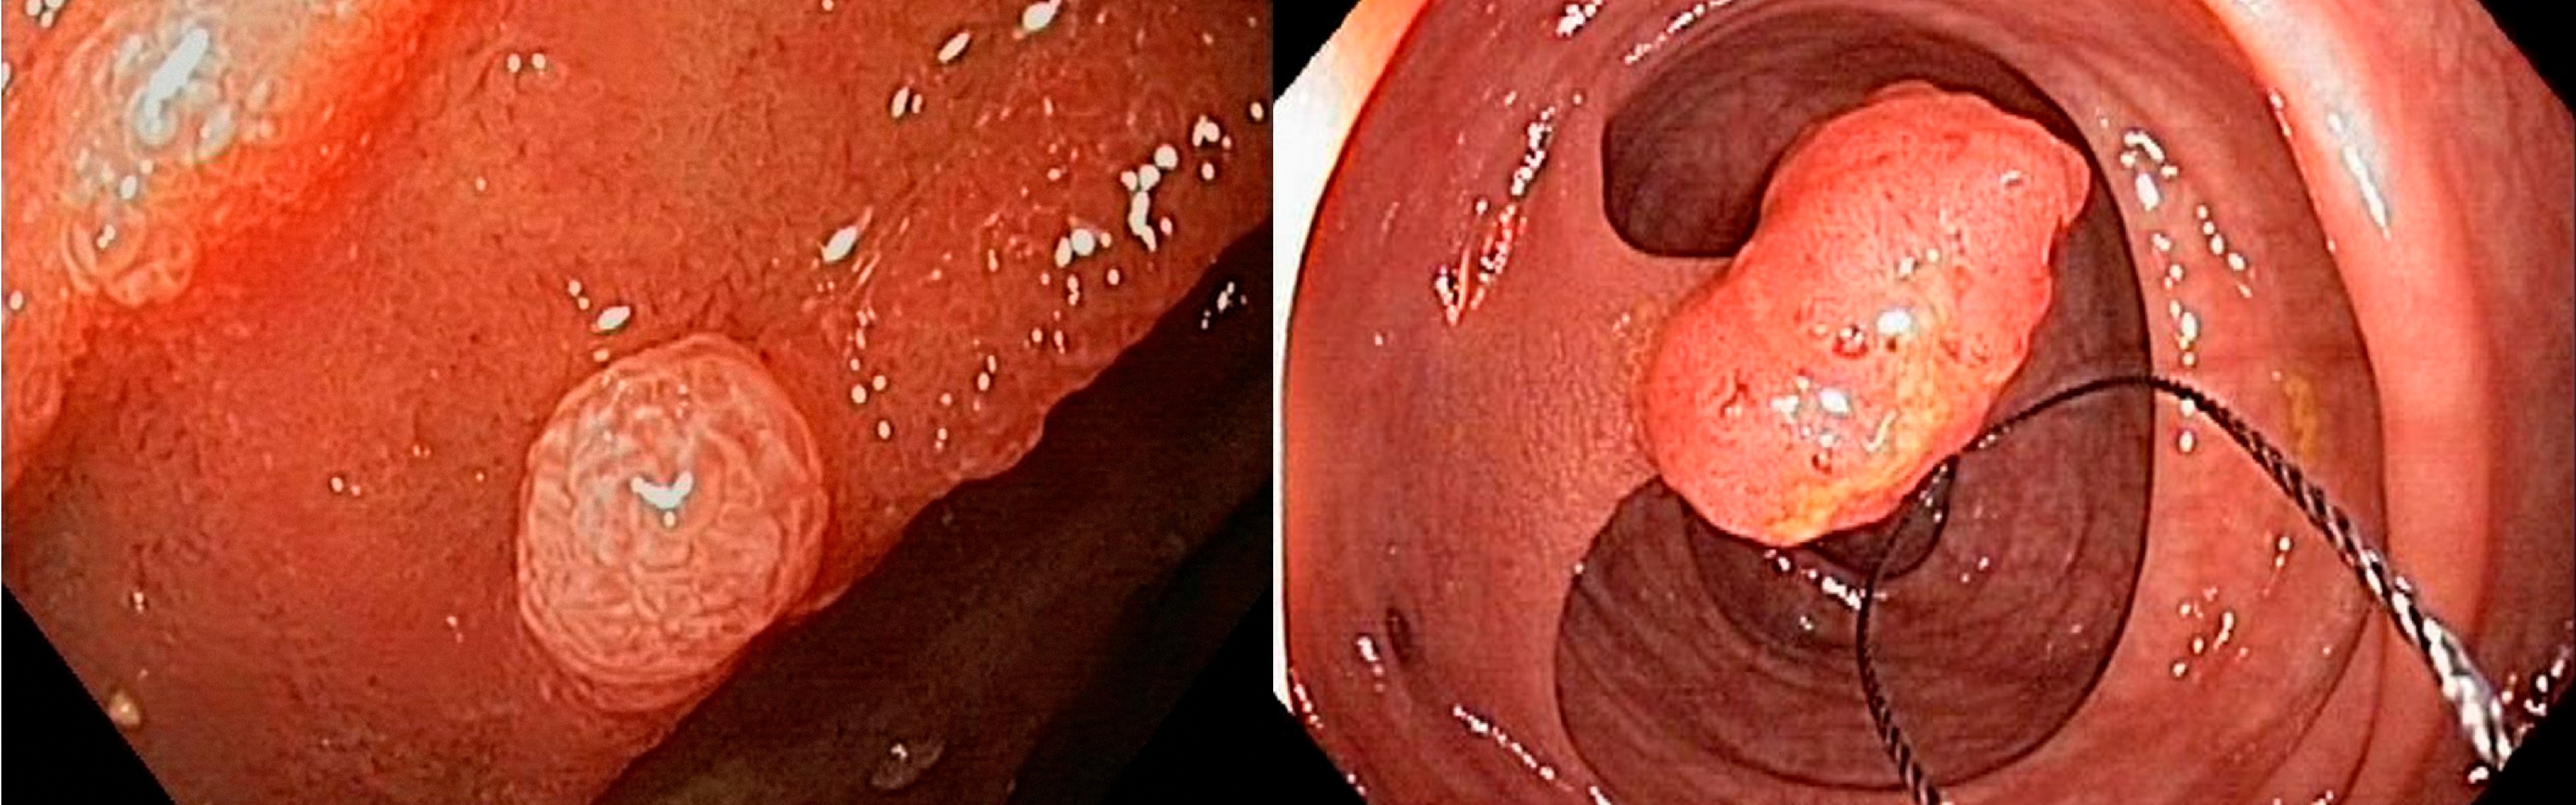

대장 내부를 직접 관찰하여 대장 용종이나

대장암 등의 질환을 진단할 수 있습니다.

필요 시 조직검사 및 용종 절제 등의 시술도

함께 진행할 수 있습니다.

선종성 용종은 일부에서 시간이 지나면서 암으로 진행할 수 있어 제거가 권장됩니다.

대장 질환 진단 뿐만 아니라, 용종 절제술과 같은